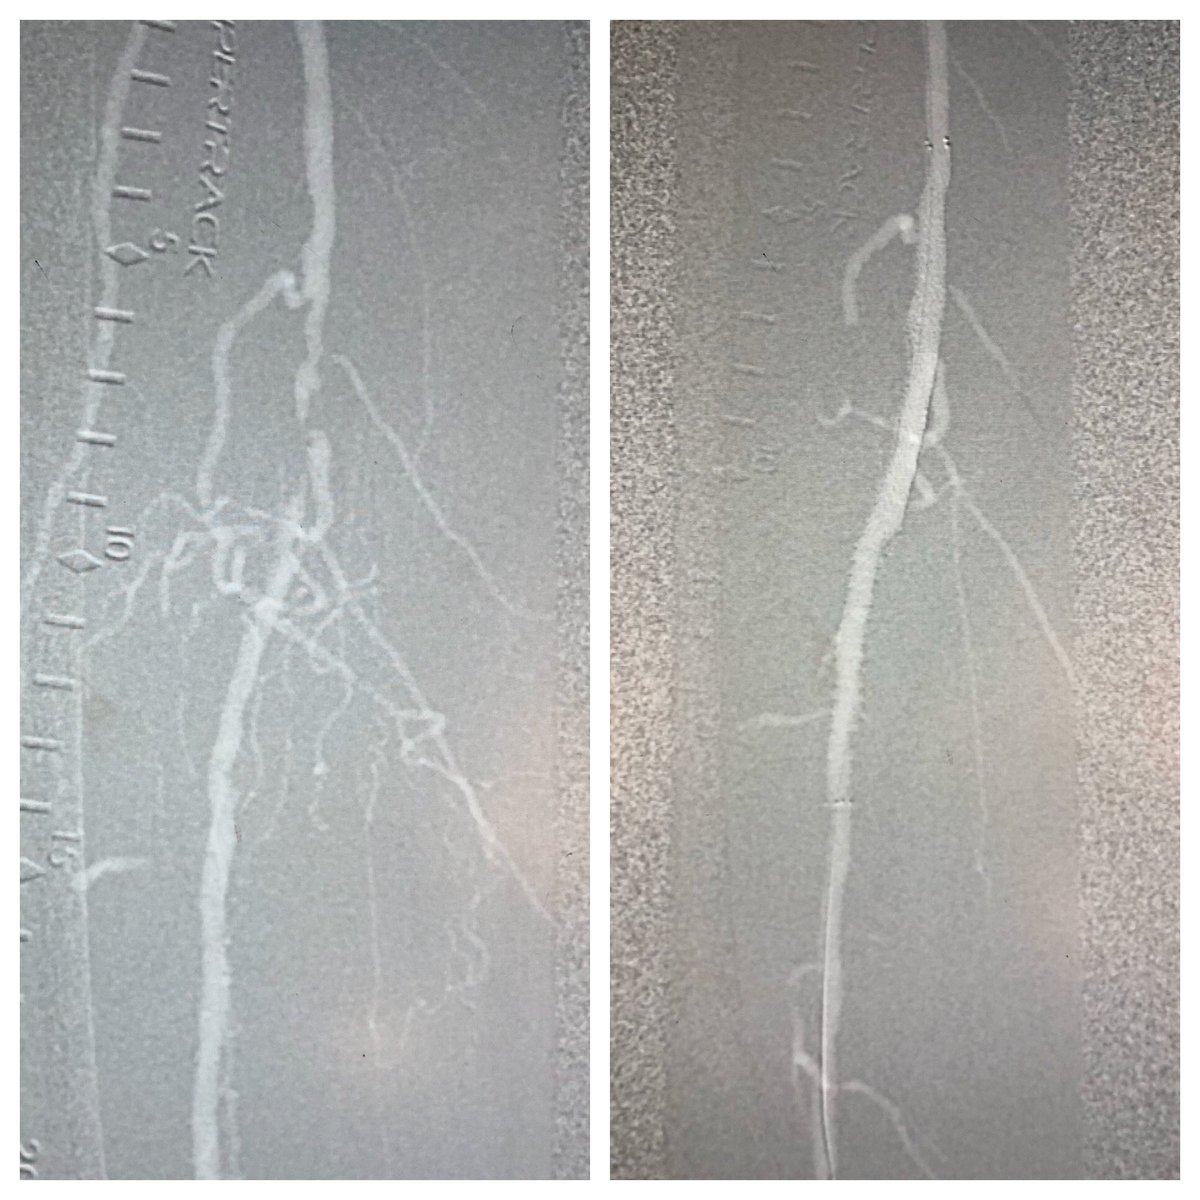

62 y/o WM T2DM, CKD w/ Cr 2.6 and right foot ulcer/osteo referred for ultra low contrast angiogram/intervention. CO2 angiography and IVUS to for vessel size/lesion length. #Eluvia w/ excellent result. Minimal (<7cc) contrast for final BTA angio #savethebeans #savealeg #SCAIPAD

matheenkhuddus's tweet image. 62 y/o WM T2DM, CKD w/ Cr 2.6 and right foot ulcer/osteo referred for ultra low contrast angiogram/intervention. CO2 angiography and IVUS to for vessel size/lesion length. #Eluvia w/ excellent result. Minimal (&amp;lt;7cc) contrast for final BTA angio #savethebeans #savealeg #SCAIPAD